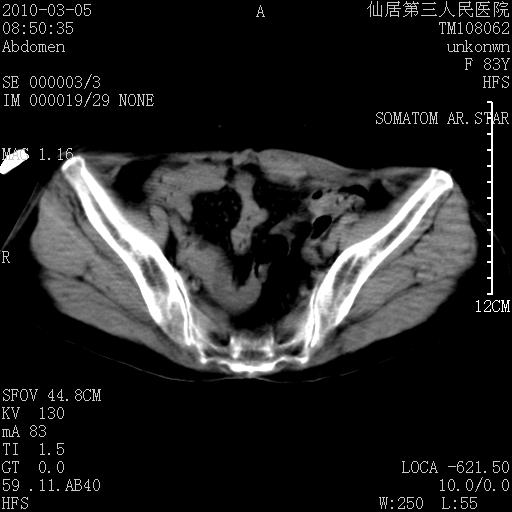

标题: CT24879:腹直肌病变。在线等。

女性,83y,腹痛一周。

考虑:左侧腹直肌神经纤维瘤可能

神经纤维瘤—伴有出血?

有无外伤,血肿或韧带样瘤

考虑左侧腹直肌血肿,肿瘤性病变待排。

增强看看,mfh可能性大,次之可考虑血肿、bfh、转移瘤、神经纤维瘤、侵袭性韧带样纤维瘤等。肝内钙化灶,右肾结石。

支持腹壁纤维肉瘤

血肿,纤维瘤,子宫内膜异位都有可能。